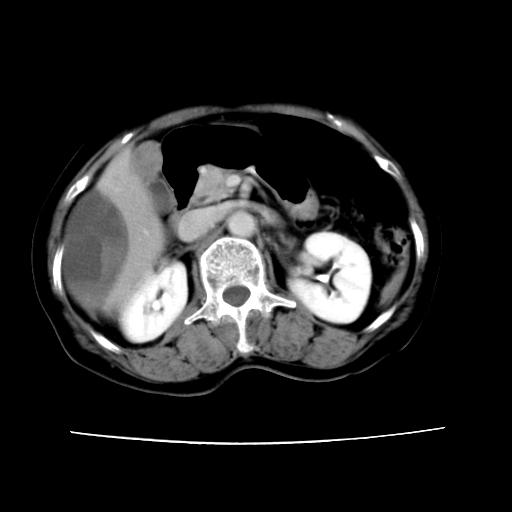

标题: CT16642:男62岁,突发性上腹部疼痛来诊。请讨论!

2008-6-10ct平扫

ct增强

6月份ct片显示肝内巨大混杂密度团块,伴包膜下积液(内含液液平面),增强多无明显强化。只能考虑肝占位病变,并肝内、血膜下血肿。肝ca并出血多见,而肝血管瘤并破裂出血少见。

6月份ct片显示肝内巨大混杂密度团块,伴包膜下积液(内含液液平面),增强多无明显强化。只能考虑肝占位病变,并肝内、包膜下血肿。肝ca并出血多见,而肝血管瘤并破裂出血少见。